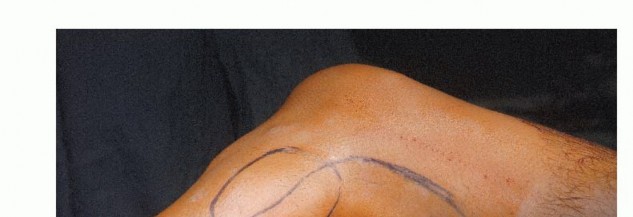

وضعية المريض

يُستخدم وضع شبه الاستلقاء (رفع الجانب الذي سيتم إجراء الجراحة عليه بزاوية 45 درجة) للسماح بالوصول السهل إلى الحجرات الأمامية والجانبية، وكذلك للسماح بتشريح المساحة المأبضية. يتم تضمين الطرف بأكمله، من الرباط الأربي إلى القدم، في الحقل المعقم. هذا يسمح بتقييم نبضات القدم البعيدة وتنفيذ بتر فوق الركبة إذا لزم الأمر، على الرغم من أن هذا نادر الحدوث بفضل التقنيات الحديثة.